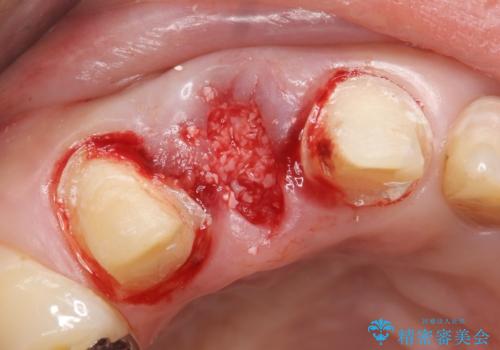

このまま右上2の抜歯を行うとさらに歯茎が下がる恐れがあったため、歯の挺出によって骨レベルを回復した上で抜歯し、歯槽堤保存術(抜歯窩に人工骨を填入する手術)を行いました。

その後ブリッジによる補綴を行うことで、自然な見た目を再現することができました。